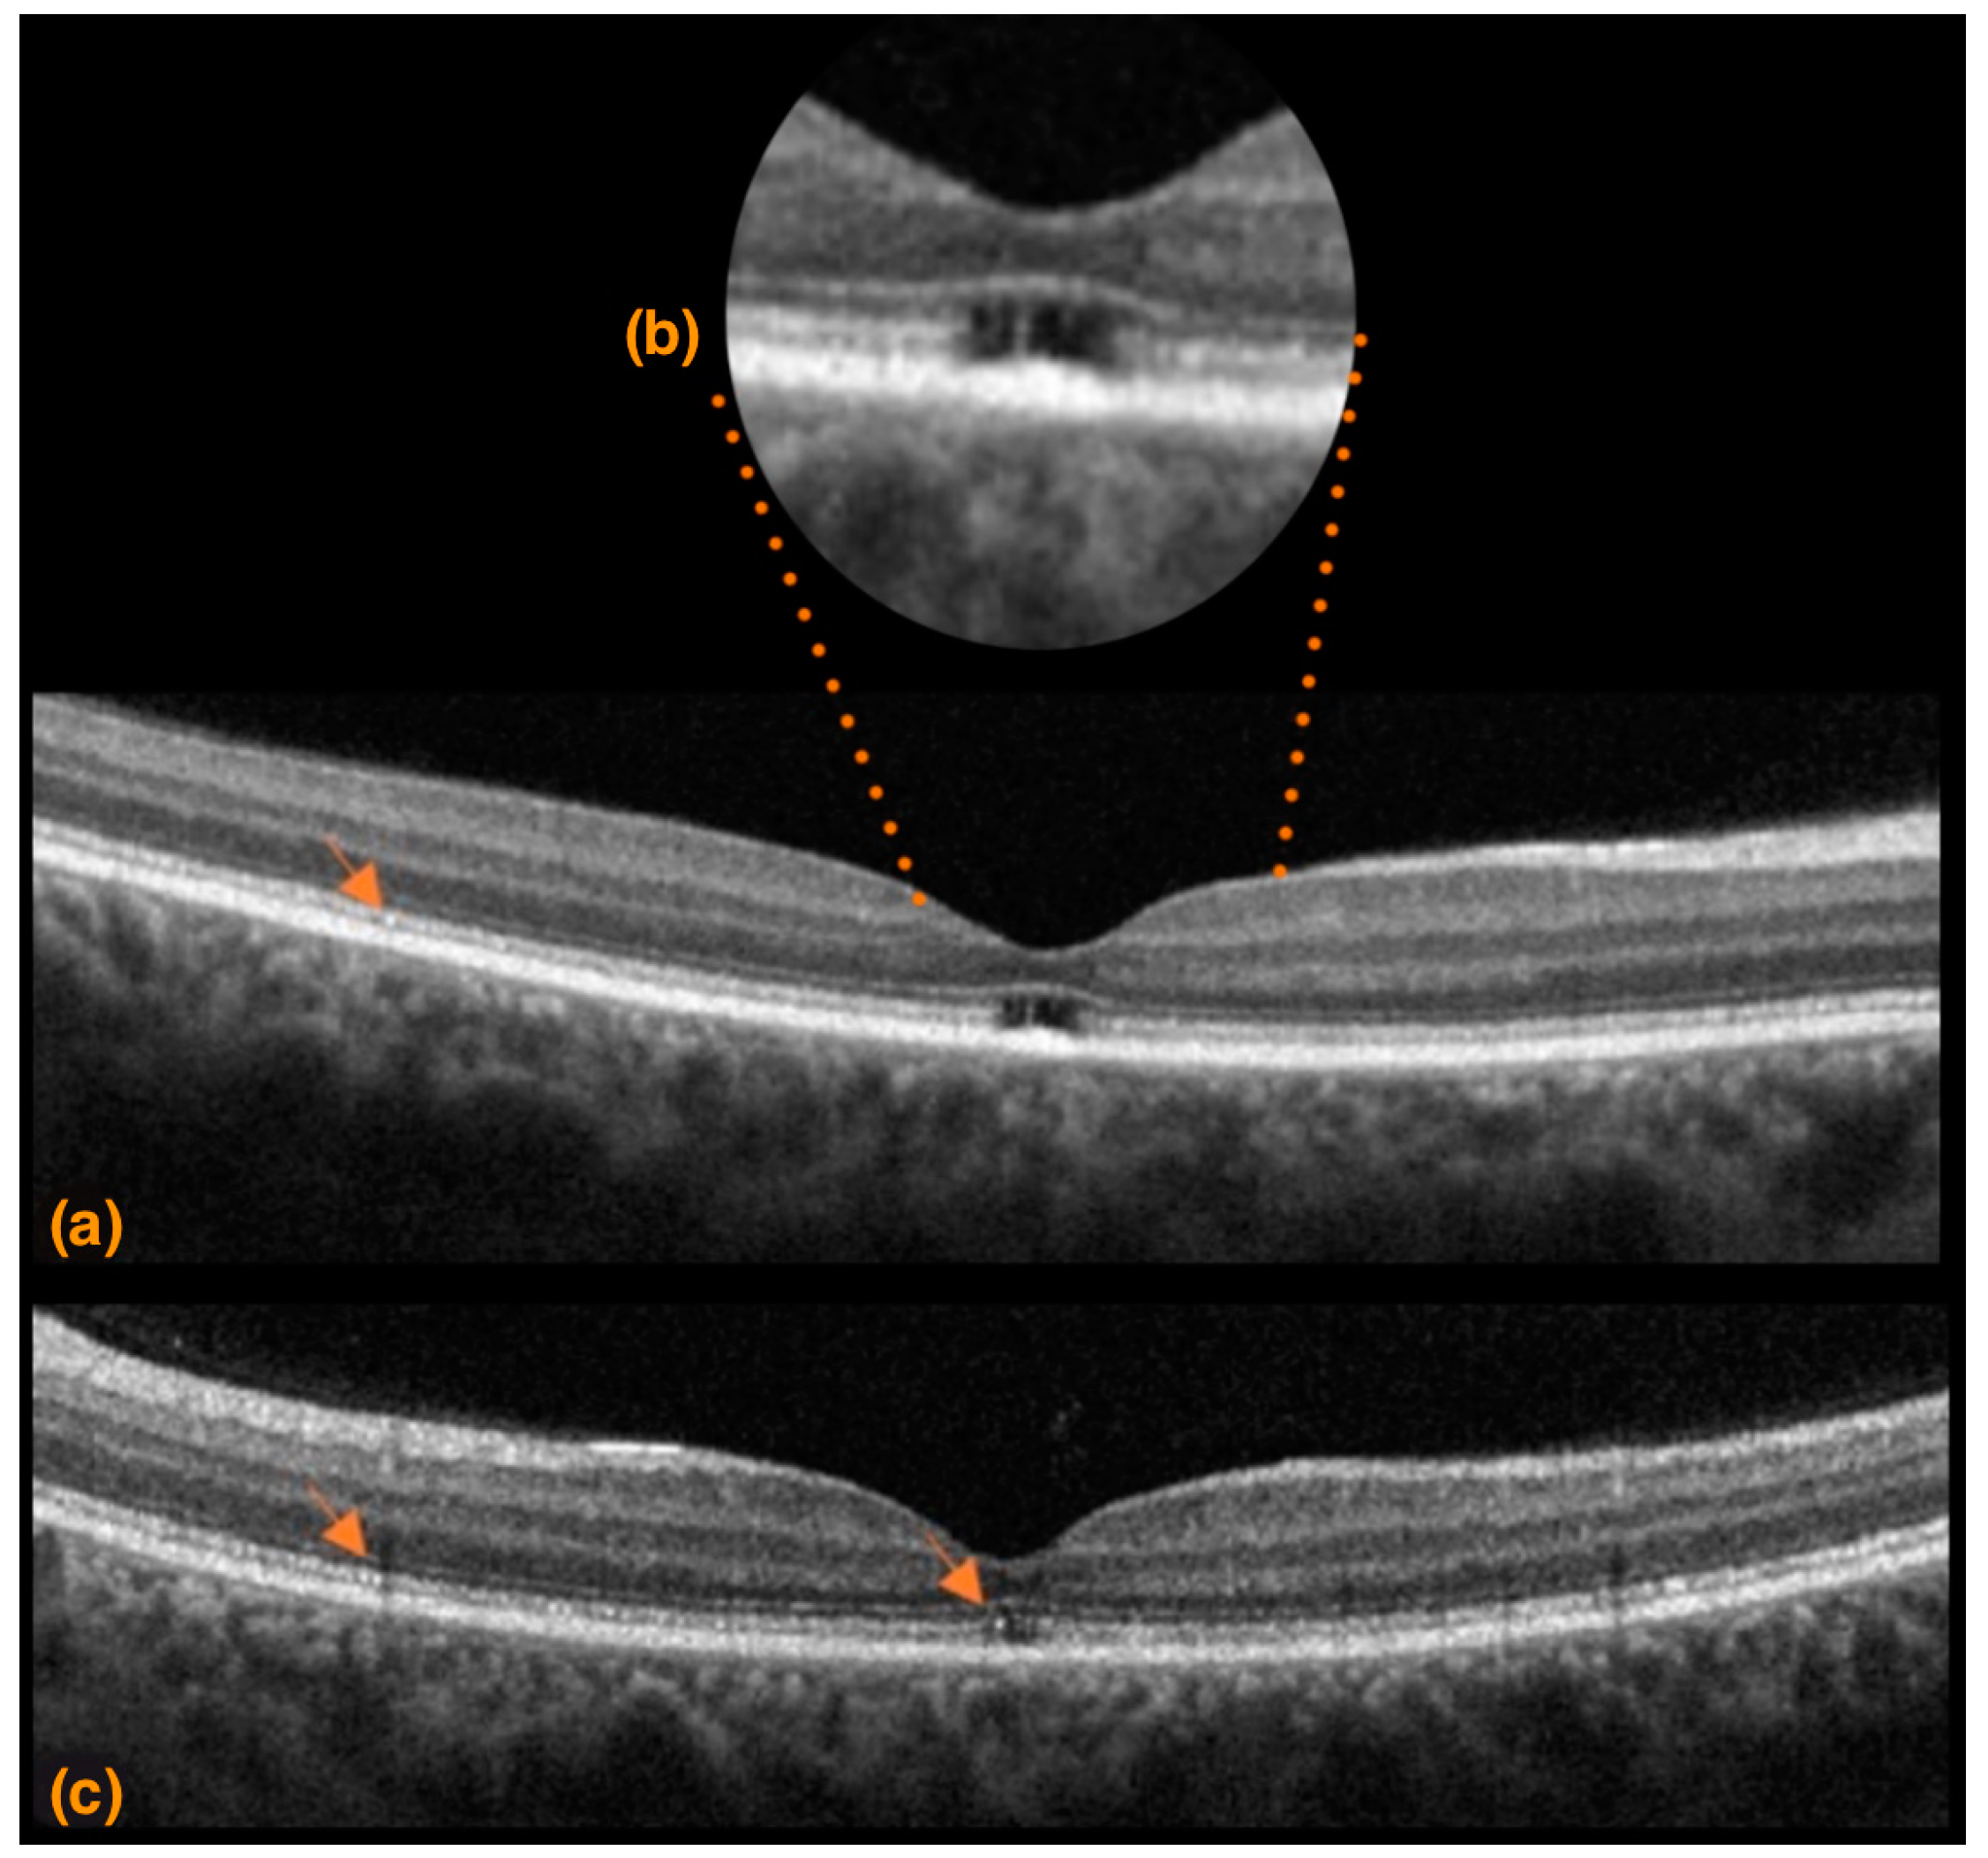

3.1. Case 1

3.2. Case 2

3.3. Case 3